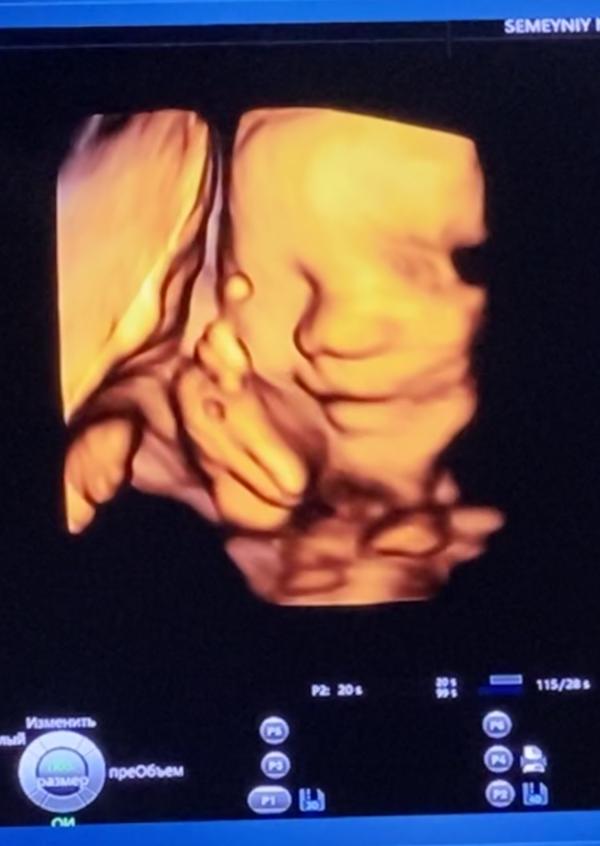

Привет 👋 #декрет #30недель 😁 Наконец-то мы добрались до УЗИ и увидели малышку 😍она такая забавная, все время улыбалась, потом закрылась ручкой и отвернулась 😁типа хватит 👌😉 Врач узи сказала- какая симпатичная малышка 🤗😍😉👌выходим на финишную прямую🙏🏼